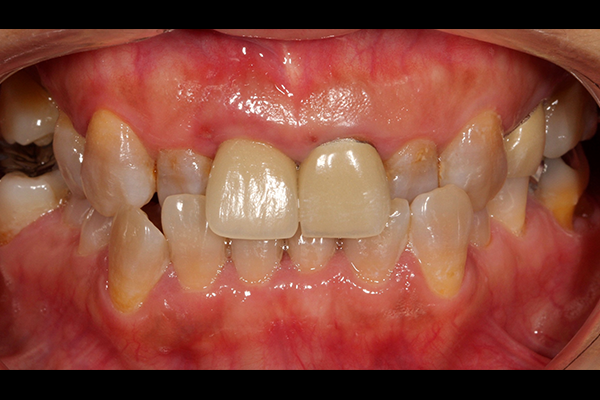

主訴は「全ての歯を綺麗に治したい」とのことで来院されました。診断の結果、複合的な問題が見つかり、歯周病治療、矯正治療等複数の治療を約3年ほど順番に進めていきました。最終的には歯の色味も回復させることができ、患者さんにも満足していただけました。

| 患者 | 45歳 女性 |

|---|---|

| 主訴 | 前歯が取れた。 |

| 診断 | このケースはかなりひどい叢生があり、矯正治療が必須であると説明。 |

| 治療内容 | 左上5は保存不可能のため、右上より5を左上に移植 矯正終了後補綴治療 |

| 治療期間 | 約3年半 |

| 費用 | 200万円 |